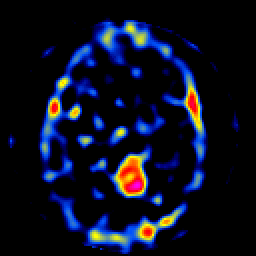

SPECT TL Study #8 -- Slice #30

[Home][Help][Clinical][Tour 1][Tour 2][Tour 3] Slice 30